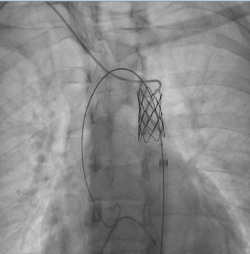

Михаил Ташник, интервенционный кардиолог: «Операция проходила в нашей лаборатории ангиографии катетеризации сердца, длилась полтора часа под общей анестезией для удобства пациента и врачей. Через небольшое отверстие на уровне артерии ноги была введена специальная трубка до уровня сужения, где в месте коарктации был имплантирован стент. Стент представляет собой водонепроницаемую медицинскую сетку, которая не только снижает степень сужения, но и сводит к минимуму любой риск возникновения разрыва аорты. Результаты и успешность случая пациентки стали возможны благодаря совместной работе врачей Medpark и коллег из Турции».